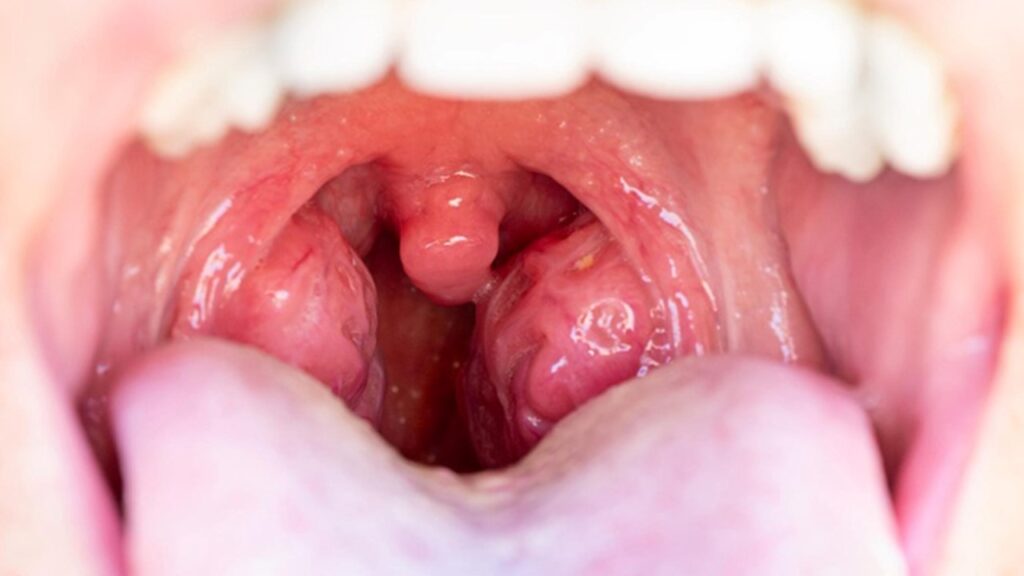

Tek taraflı bademcik şişmesi

Tek taraflı bademcik şişmesi, boğazın yalnızca sağ ya da sol tarafındaki bademciğin belirgin şekilde büyümesi, ağrıması ve çoğu zaman iltihaplanması durumudur. İki taraflı bademcik şişmesi daha sık görülse de, tek taraflı olan durumlar daha dikkatli değerlendirilmesi gereken bir tablo olarak kabul edilir. Çünkü bazı durumlarda basit bir enfeksiyonun ötesinde, apse ya da farklı hastalıkların habercisi olabilir.